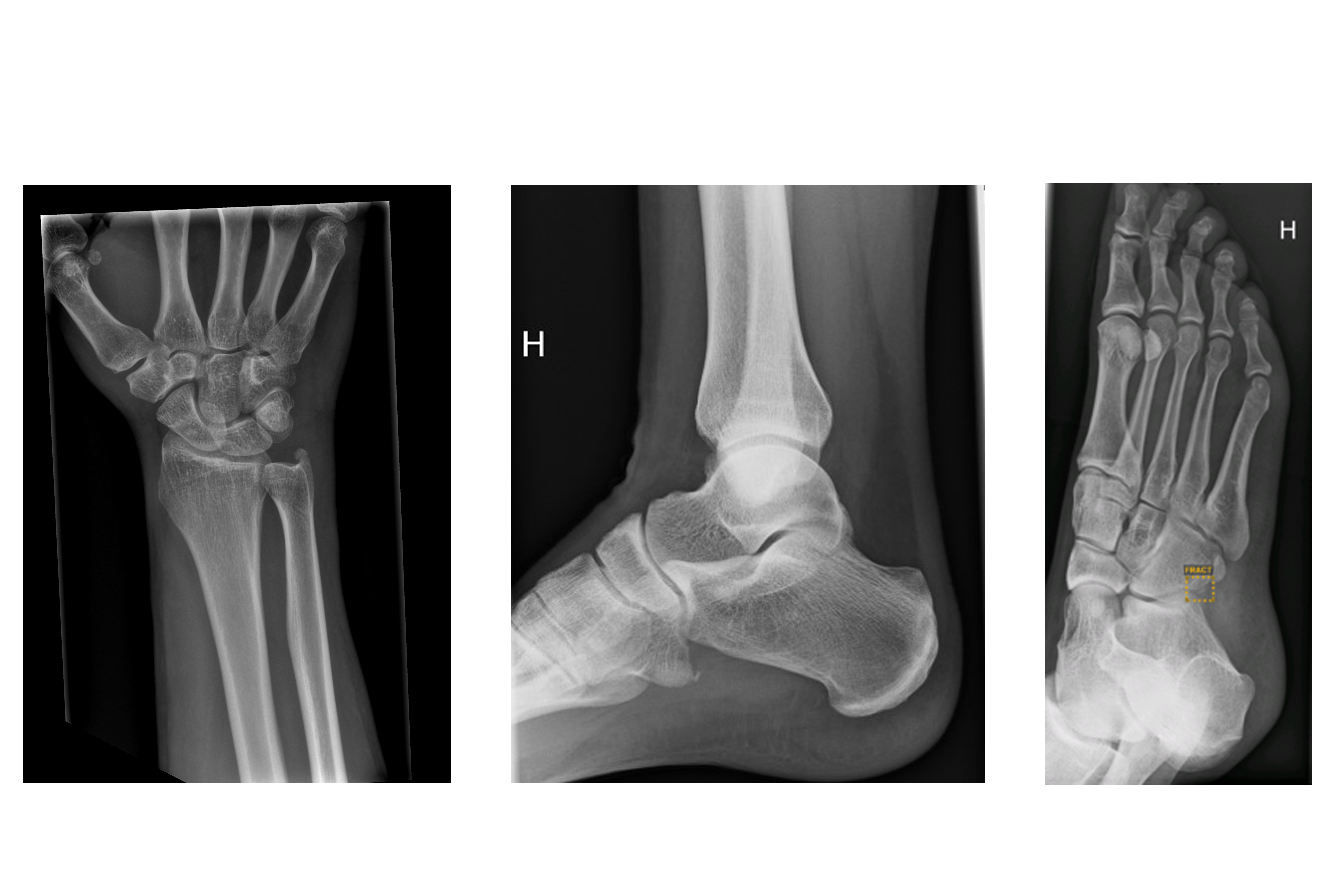

- Dagens medisin - Her er første fot som er diagnostisert med kunstig intelligens i Vestre Viken

- TV2 - Finner brudd som legene overser. Først i Norge med å teste dette

- VG - Fikk hånden analysert av kunstig intelligens - resultatet kom så raskt

- Eikerbladet - Line fra Ormåsen er den første i landet